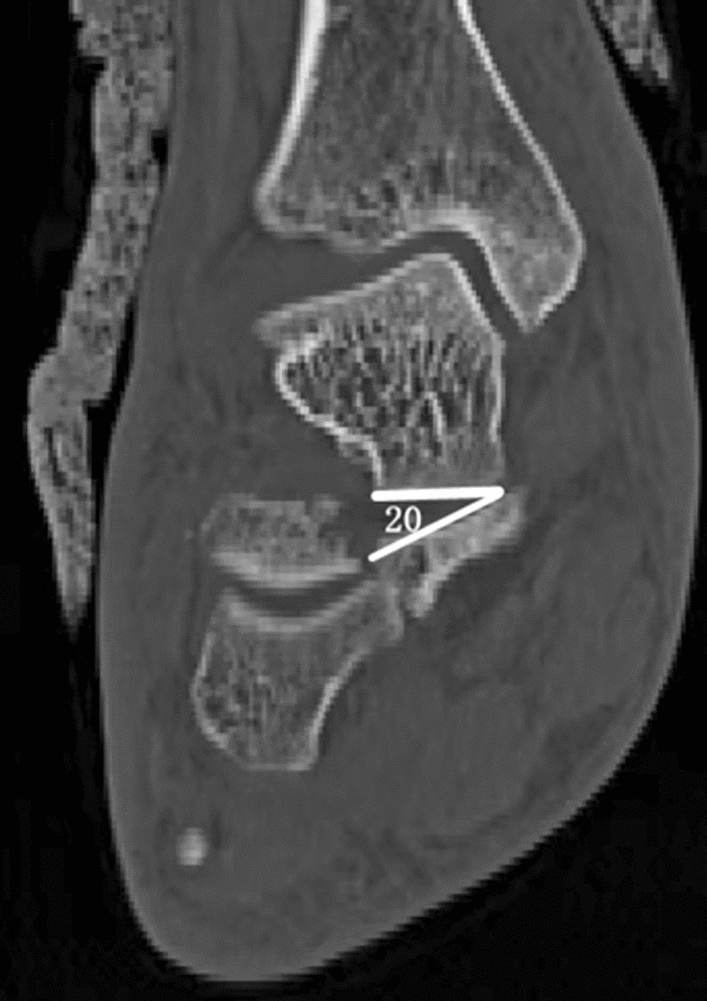

Figure 2.

Coronal CT showings the angulation of the sustentaculum fragment.

Raw CT data were transferred into Mimics 21.0 software (Materialise) and were reviewed and independently assessed by two professional radiologists. Previous studies have indicated that the sustentaculum tali comprise approximately one-third of the transverse width of the calcaneal, with an average length of 13 mm in the transverse plane of the calcaneus14. Consequently, we designated the sustentaculum tali as the 13-mm-long extension of the most medial prominence. And CT scans of non-displaced calcaneal fractures served as controls for determining the normal limits of measuring parameters and the ideal CT cuts for evaluating various metrics (Fig. 1). By analyzing the prevalence and displacement of sustentacular pieces in coronal and sagittal planes using measurement angulation, subtalar dislocation was determined. Any angulation exceeding 10° and translation of more than 2 mm, and the displacement diagnostic has been considered. Angulation > 5° of articular surfaces were considered subluxation. Sustentacular fracture, displacement, and dislocation of the talus sustentaculum were documented2 (Fig. 2).

Coronal maps

The sustentaculum tali are predominantly formed by cortical bone, with high trabecular bone density, which provides solid medial support throughout Surgical fixation24,26. In this study, 6 (28.6%) were displaced, the mean coronal angulation was 21.9°, and the subluxation was 10 (12.3%). This may be related to the internal structure of the sustentaculum tali, which lacks a comminution area. Furthermore, the fracture patterns revealed in our study may enhance the understanding of injury associated with the sustentaculum tali. In our research, 6 (28.6%) were displaced, of which displaced Sanders IV accounted for 5 (83%), with a subluxation in 10 (12.3%). Our results indicate that the surrounding ligaments were probably to have been injured, challenging the notion that the fragments are anatomically consistent and integrated with the talus via the interosseous and deltoid ligaments. Hence, when preoperative CT scans reveal displacement or subluxation of the sustentacular fractures, we advise further MRI evaluation to establish the damage condition of the interosseous and deltoid ligaments.